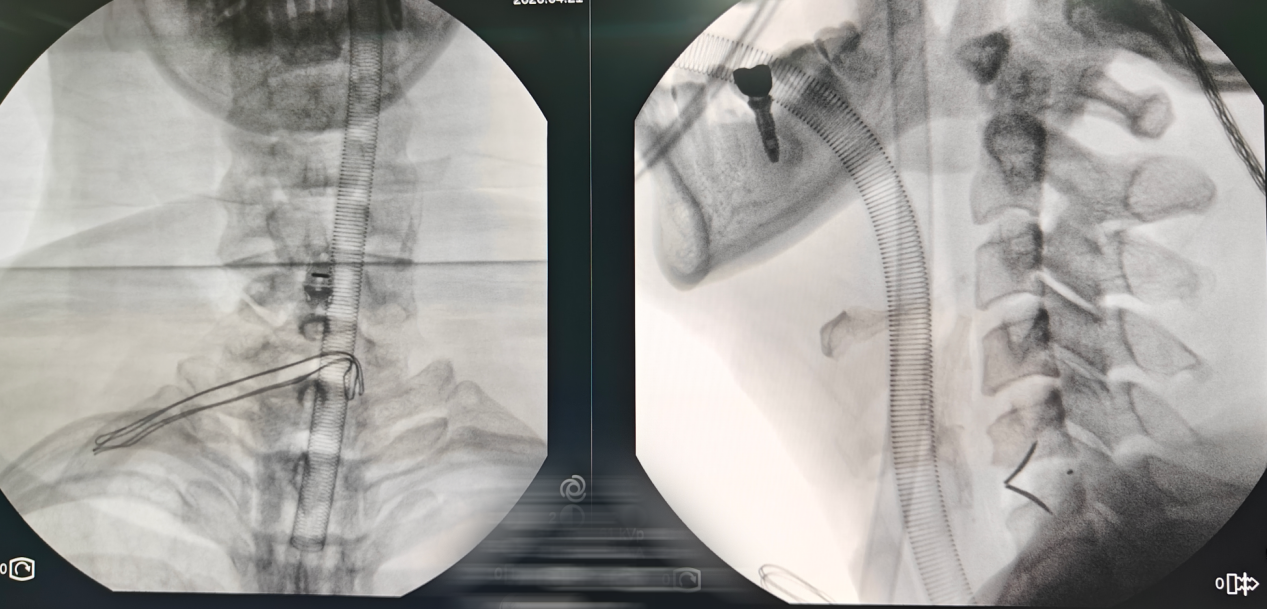

术后影像:

在C5/C6节段做长约2.5cm横行切口,在显微镜下,进行椎间盘切除,椎管减压,然后置入Uni-C 插片式颈椎自稳定型融合器。